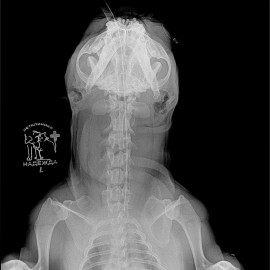

Собаке был поставлен диагноз: экструзия диска на уровне С3-С4, протрузия диска С6-С7.

Собаке была проведена операция: Фенестрация при помощи вентральной щели на уровне С3-С4.

Снимок 2 после операции.